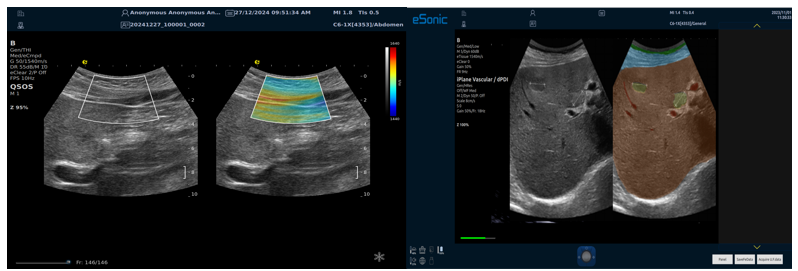

平面波超微细血流显像

彩色多普勒成像、3D壁滤波原理

血流敏感度明显提升,分辨率达微米级别

支持灰阶和微血流量同步测量、可测极低速血流的速度

多种模式,多数据定量评估。

RTSWE实时剪切波弹性成像

?探头发射激励脉冲进行多点动态聚焦,利用马赫圆锥原理,形成大量的剪切波信号?颜色的变化与剪切波的速度相关,可直接体现肌肉肌腱等组织硬度值?实时、全幅、全定量

鉴别诊断、精准分级、定量评价、穿刺引导、疗效评估、随访观察

QSOS声速定量成像

测量原理

QSOS声速成像技术利用声波在组织中的传播速度差异性,计算不同位置的声速值,反映组织的物理特性。

成像过程

利用超声探头发射超声波脉冲,分析反射信号的时间延迟,确定声波传播路径和速度,构建声速分布图像。

图像显示

QSOS技术采用彩色编码显示声速图像,不同颜色代表不同声速值,便于医生识别病变部位和测量。

技术优势

?精准定量反映组织特性,成像更敏锐?彩色编码直观显示,轻松发现异常?捕捉声速差异,早期、微小病变更易察觉

肌骨领域的应用

?精准定位损伤部位?判断损伤严重程度?监测肌肉营养?评估肌少症?骨质疏松评估